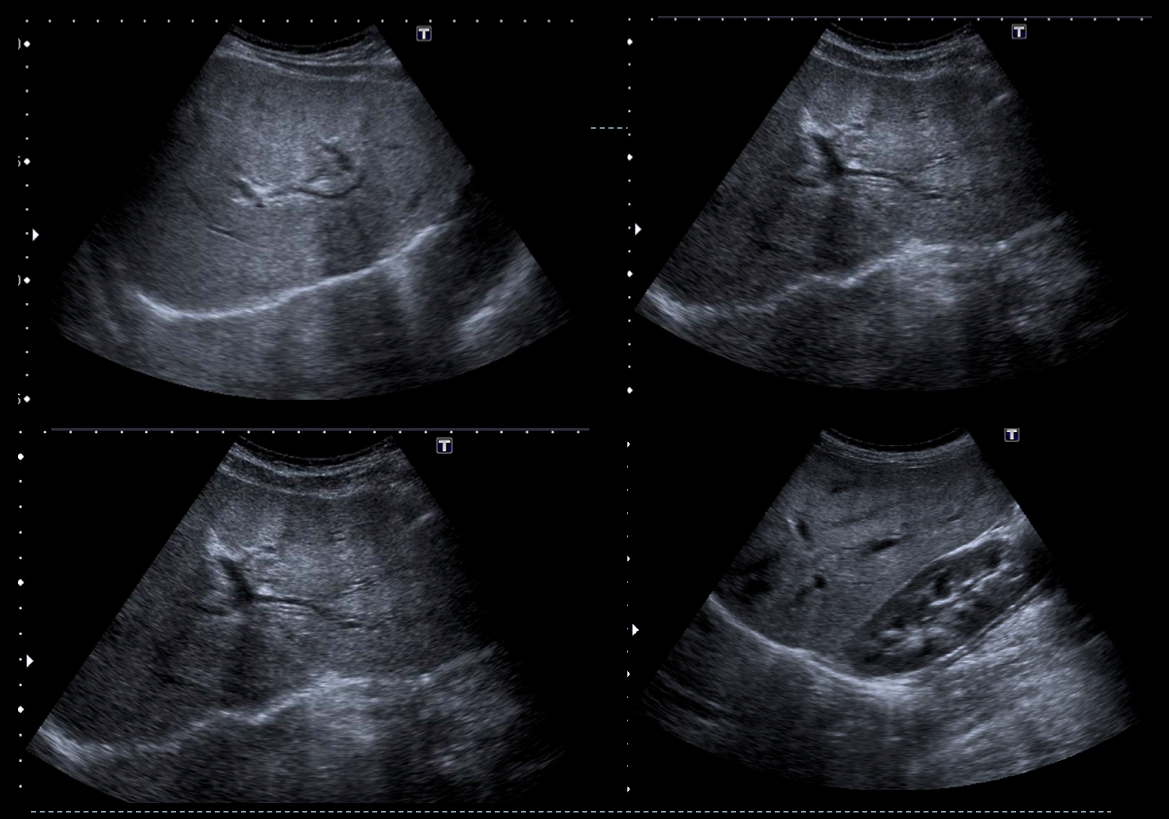

• Ecografía abdominal.